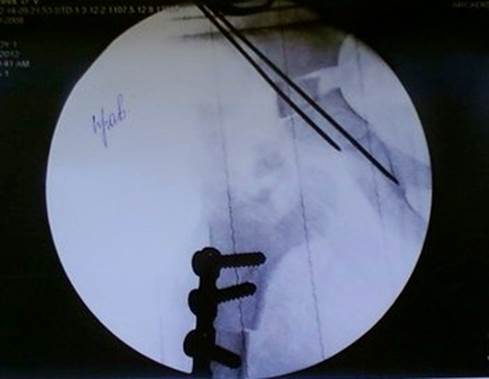

Данные интраоперацинного Rtg-исследования (14.02.2012)

Головка правой бедреной кости центрирована в вертлужную впадину. Фрагменты правой бедренной кости скреплены пластиной с шурупами.

Разрез 8 см. от верхней трети правого бедра вниз по наружной поверхности до бедренной кости. Произведена деротационно-укорачивающая остеотомия бедра на границе верхней и средней трети на 1, 5 см., остеосинтез пластиной на 4 винта. Rtg – антеторсия 0 градусов.

Остетомия таза по Солтеру справа с трансплантацией аутокости с кортикальным слоем из бедра в таз. Остеосинтез двумя спицами.

Открытое вправление вывиха, иссечение излишка капсулы, пластика капсулы. Rtg-контроль: вывих вправлен, покрытие головки полное, ацетабулярный индекс 15. Гемостаз, активные дренажи в раны. Послойное ушивание ран, кокситная гипсовая повязка.

Rtg-контроль: Головка правой бедреной кости центрирована в вертлужную впадину: вывих вправлен, покрытие головки полное, ацетабулярный индекс 15. Фрагменты правой бедренной кости скреплены пластиной с шурупами.